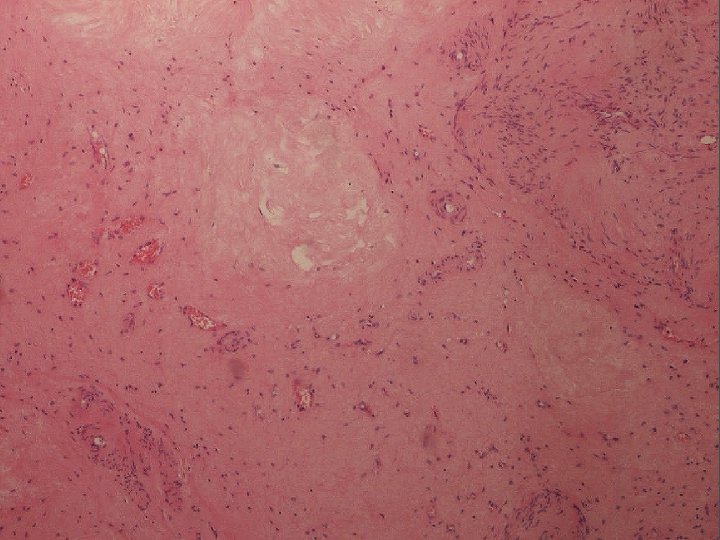

Naša diagnóza Segmentálna atrofia pečene, stage II / nodulárna elastóza pečene

Stage 1 - 4 • 1 – kolaps parenchýmu so zachovaním portálnych polí, občasnými ostrovčekmi zachovaného parenchýmu a s duktulárnou reakciou • 2 – minimálna až žiadna duktulárna reakcia, zvýšená miera elastózy • 3 – takmer výlučne elastóza, občasné malé ostrovčeky hepatocytov • 4 – end stage, ložisko fibrózy

Elastika? • v poškodených tkanivách sa môže tvoriť nadmerné množstvo (dezorganizovaných) elastických vlákien • v pečeni normálne v stenách ciev, malé množstvo v portálnych poliach a okolo centrálnej vény • pri poškodení produkujú portálne fbroblasty • prečo tak exuberantne?